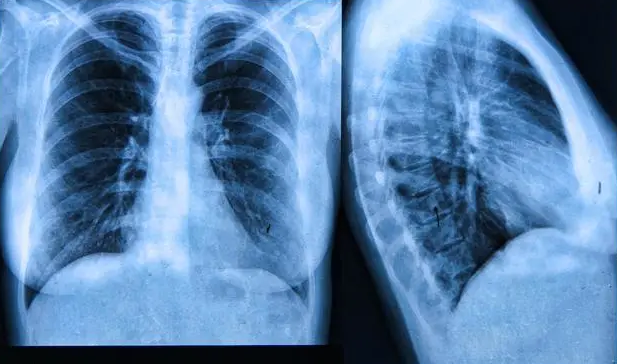

这种情况考虑与肺部结节有关,肺部结节导致肺部细胞功能下降,引起呼吸困难。建议到医院呼吸内科就医明确诊断。

要考虑是肺部结节疾患及心脏疾病,应及时去医院进一步检查,通过肺部加强CT及心电图检查明确诊断。应及时去医院进一步检查,明确具体病因,对症有效治疗,观察症状有无缓解。

可能不太像肺部结节病变导致的临床症状,问题不大,建议查心电图认识心率心律变化,建议定期复查必要及时最好去医院的呼吸内科做一个纤维支气管镜,明确发病原因,及时进行对症治疗。